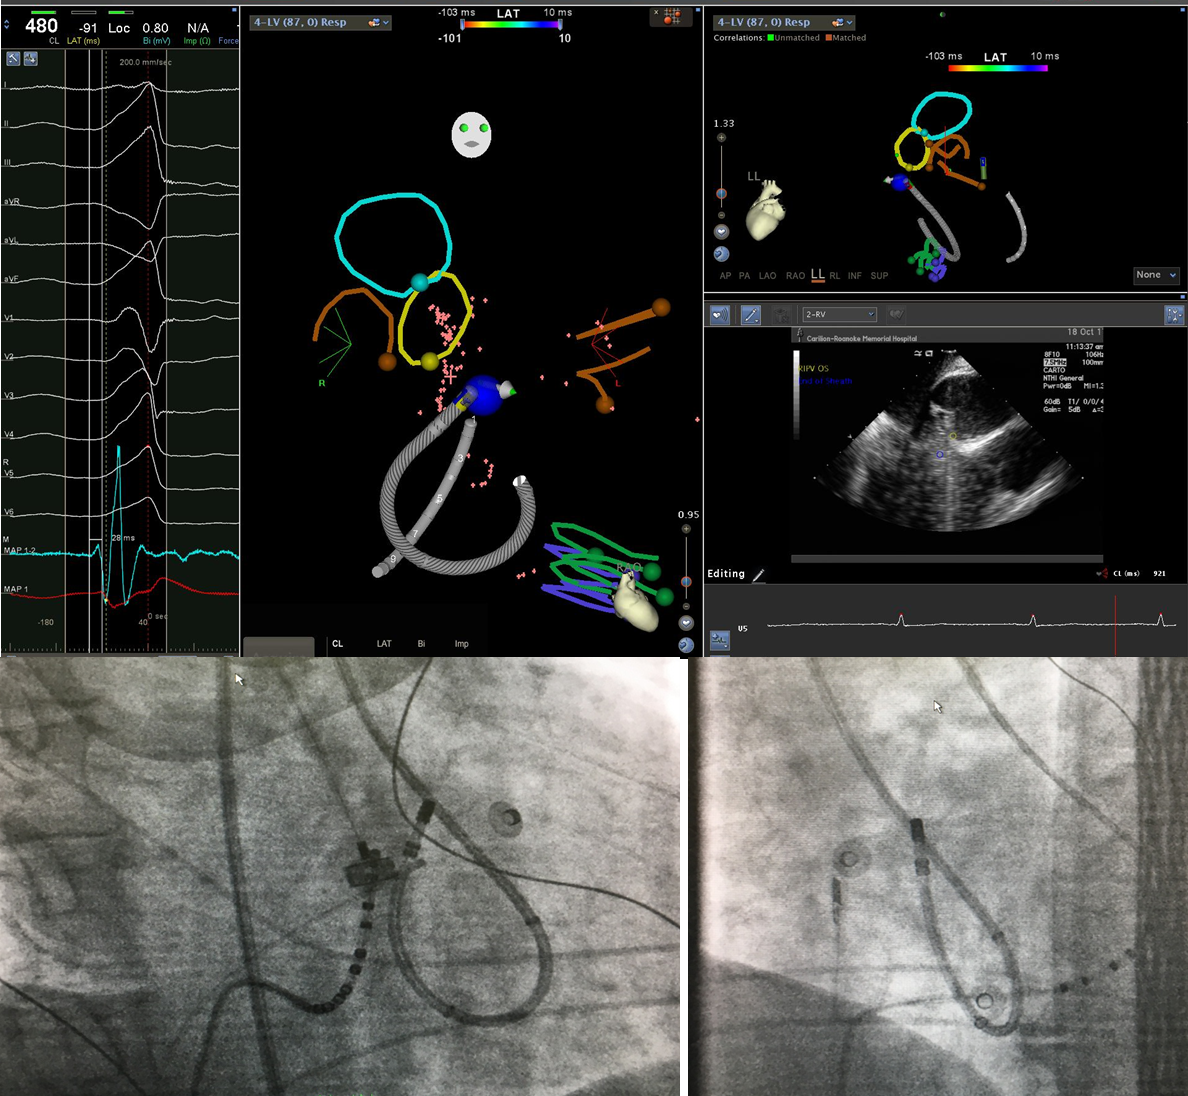

65 yo with symptomatic multifocal PVCs, ~30K, EF 45%,  3 different PVCs were ablated today..fun & require patience, thanks to the team!